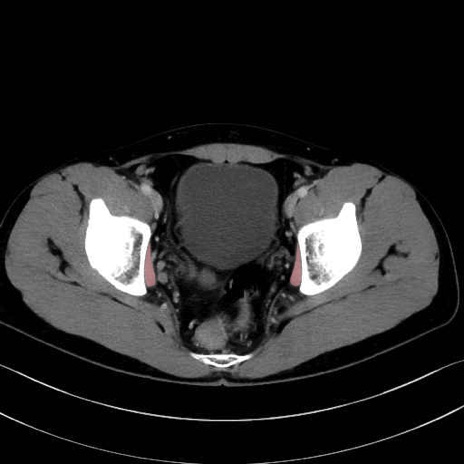

内閉鎖筋(obturator internus) のCT画像の解剖

内閉鎖筋 (Obturator internus)